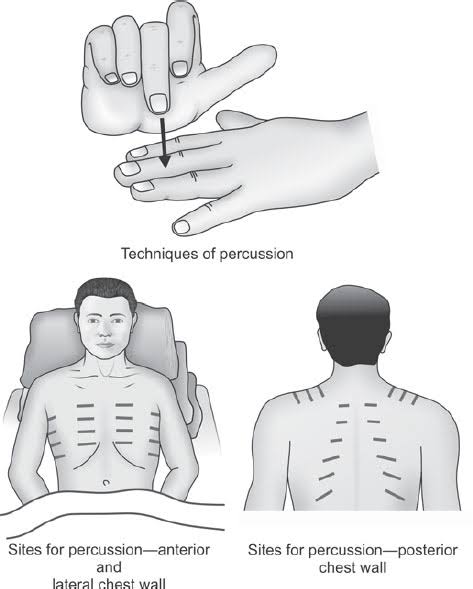

Percussion (પરકશન):

- રેસ્પાયરેટરી પરકશનમાં ચેસ્ટનું ટેપિંગ કરીને અન્ડરલાઇંગ સ્ટ્રકચરને અસેસ કરવામાં આવે છે જેથી ત્યાં એર, ફ્લુઇડ અથવા સોલીડ પ્રેઝન્ટ છે કે નહિ ચેક કરી શકાય.

- જેમાં એન્ટેરીઅર અને પોસ્ટેરીઅર ચેસ્ટને સાઇડ ટુ સાઇડ અને ટોપ ટુ બોટ્ટમ ટેપિંગ કરવામાં આવે છે અને તેના દ્વારા સાંભળવાં મળતા સાઉન્ડને નોટ કરવામાં આવે છે.

- આ ઉપરાંત રેસ્પાયરેટરી પરકશનમાં રેસ્પાયરેટરી એક્સકરસન નોટ કરવામાં આવે છે.

- રેસ્પાયરેટરી પરકશન એ લંગ ડેન્સિટીમાં જોવા મળતા ચેન્જીસને આઇડેન્ટીફાય કરવા તેમજ ન્યુમોનિયા, પ્લુરલ ઇફ્યુઝન જેવી કન્ડીશનને ડાયગ્નોસીસ કરવા માટે ઉપયોગી છે.